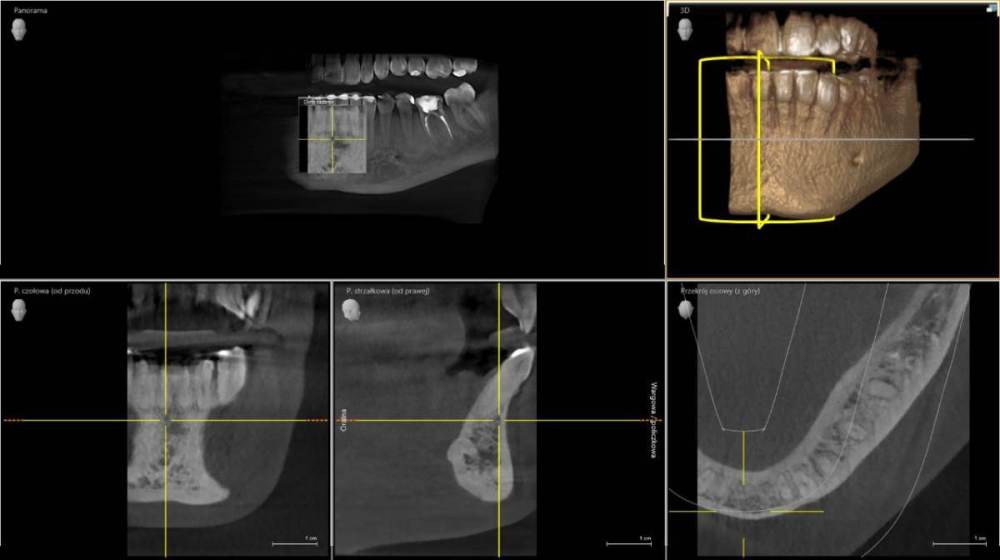

chacraborti Опубликовано 25 января, 2023 Поделиться Опубликовано 25 января, 2023 (изменено) Врач говорит что под пятеркой воспаление, квалифицирует зуб к лечению каналов. Прав ли врач? Можно ли вылечить воспаление иначе? Антибиотиками? Через кость? Через лунку при удалении рядом находящейся шестерки без нервов (она квалифицирована к удалению)? Субъективно время от времени в том районе чувствую слабую тупую боль которая может продолжаться несколько дней. потом исчезает, иногда стреляет(бывает раза 2 в день) время от времени, когда ем мороженное в том месте как будто щелкает Изменено 25 января, 2023 пользователем chacraborti Ссылка на комментарий

red_butler Опубликовано 26 января, 2023 Поделиться Опубликовано 26 января, 2023 5 часов назад, chacraborti сказал: Прав ли врач? если судить только по снимкам и Вашим жалобам то прав. Холодовую пробу проводили? 5 часов назад, chacraborti сказал: Через лунку при удалении рядом находящейся шестерки без нервов (она квалифицирована к удалению)? по снимкам вполне лечибельный зуб Ссылка на комментарий

chacraborti Опубликовано 26 января, 2023 Автор Поделиться Опубликовано 26 января, 2023 Цитата Холодовую пробу проводили? Холодовую пробу не проводили, жалоб врачу не озвучивала (прием был о судьбе шестерки). Врач квалифицировал пятерку к лечению каналов ориентируясь только на снимки: панорамный и маленький. Стоит провести холодовую пробу чтобы определить какой зуб вызывает мои жалобы? Ссылка на комментарий